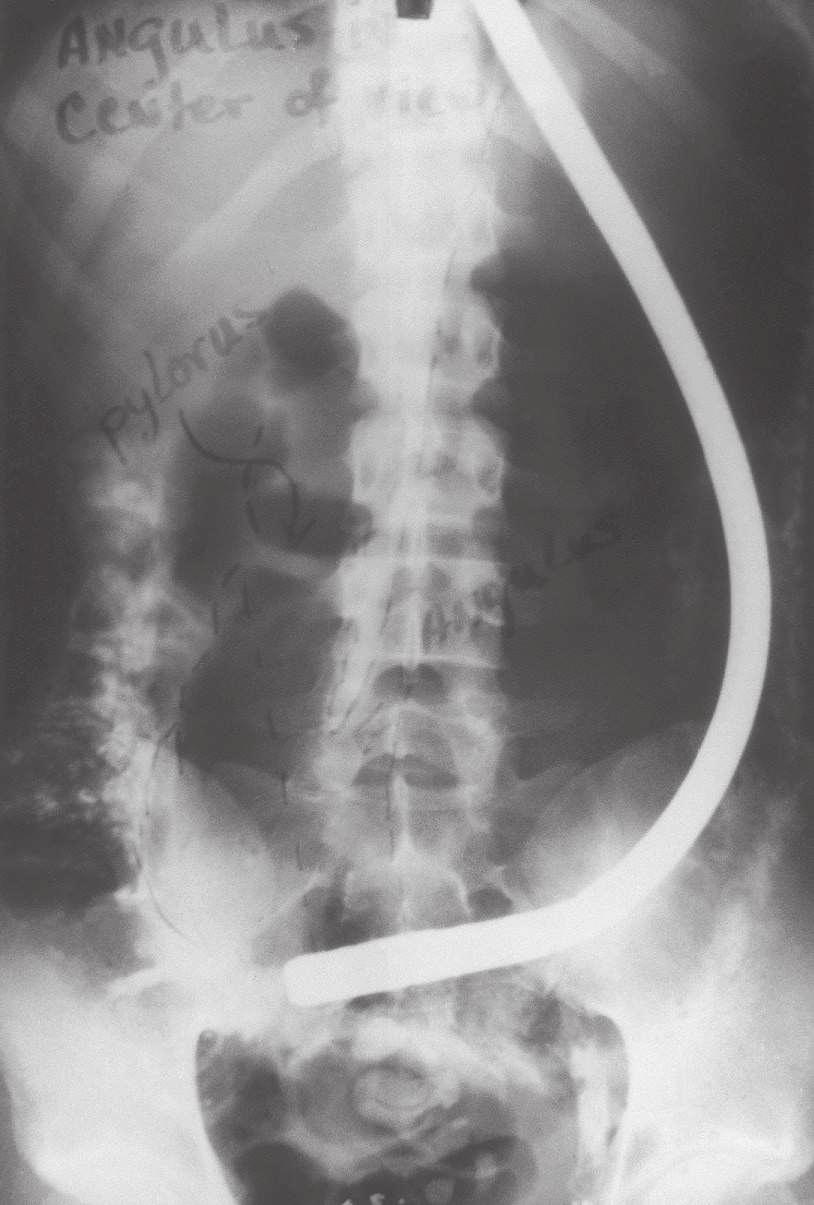

There were problems with the fiberscope noted by users. The distal light source would become so heated that thermal injury to the gastric mucosa was possible unless the tip was continuously moved. In prolonged procedures, protein in gastric secretions would coagulate on the bulb and the adjacent visualizing port, totally obscuring the lens. As the number of procedures with a single instrument increased, some glass fibers would break, producing small black dots in the visual field. This was a persistent problem with fiberscopes during their entire history and especially apparent in training programs where a single scope was used by several trainees on many patients. The side-viewing lens prevented visualization of the esophagus, and the scope had to be passed blindly through the pharyngeal orifice. The previous semiflexible scopes in use shared this problem, and it was not considered a defect at the time. The flexibility itself resulted in some difficulty in advancing because attempts to push the instrument through the pylorus and into the gut resulted in more bowing in the gastric pouch (Fig. 1.10). Although one could sometimes visualize the duodenum, this was done by overinflating the stomach and looking through the pylorus without actually entering it. If one managed to introduce the tip into the duodenum, as occasionally happened, the visual field was inside the focal length of the instrument, and only a “red-out” was observed.4

FIG 1.10 Visualization of duodenum was sometimes obtained by overinflating the stomach.